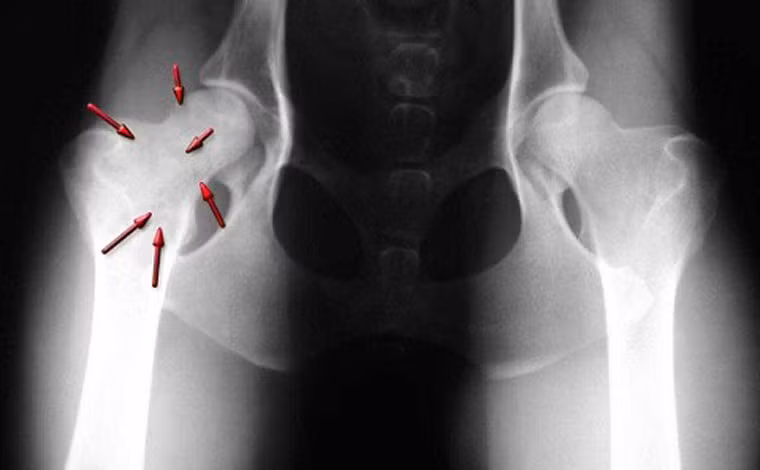

Gãy xương. Khi các tế bào ung thư phát triển trong khu vực này, nó tác động làm suy yếu xương. Ngay cả những tác động nhỏ, bất ngờ cũng khiến bệnh nhân đối diện với tình trạng gãy xương. Thậm chí, một số trường hợp khi nhập viện, các bác sĩ vẫn có thể nhầm lẫn bệnh với nguyên nhân gãy xương thông thường, tiến hành bó bột hoặc đóng đinh nội tủy.

Xuất hiện khối u. Ban đầu, khối u có thể là một đám chắc, đẩy gồ mặt da, bờ không rõ, sờ nắn không đau. Về sau to nhanh, làm biến dạng vùng có u. U thâm nhiễm tổ chức phần mềm, nổi rõ các mạch máu dưới da và tân tạo các mạch máu nhỏ, đau khi thăm khám, màu sắc da trở nên hồng, ấm hơn nơi khác, mật độ nơi mềm, nơi chắc, nơi căng do máu tụ.